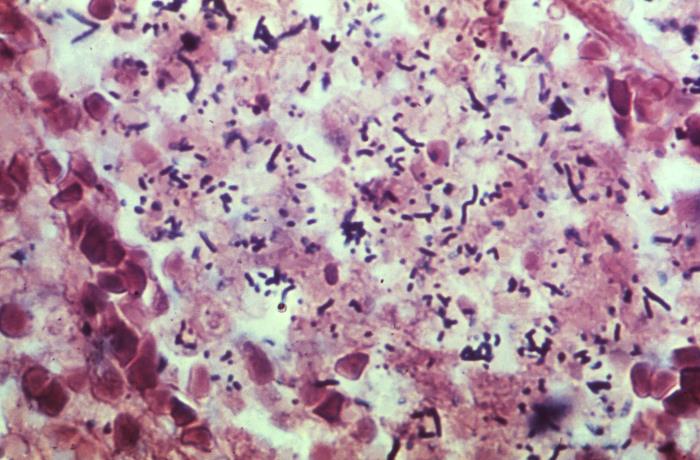

顯微鏡下的李斯特菌

生物顯微鏡下李斯特菌呈單個或短鏈狀

多數李斯特菌體***端較大,似棒狀

培養時間延長或粗糙型培養可呈絲狀菌體